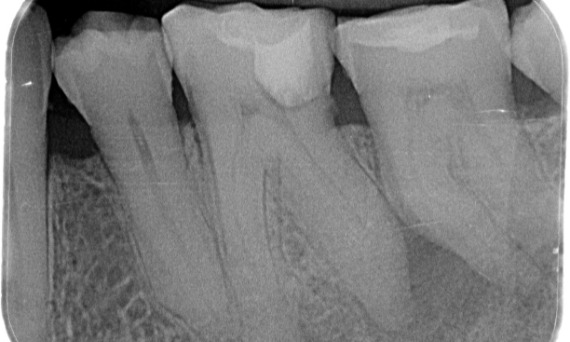

Vóór: Periapicale radiolucentie aan de distale wortel en verlies van lamina dura aan de mesiale wortel.

Vóór: Bij onderzoek werd een cariëslaesie geconstateerd aan de eerste molaar rechtsonder. Uit radiologisch onderzoek bleek dat de laesie zich nabij de pulpahoorn bevond en in combinatie met de voornaamste klacht, werd een definitieve diagnose van chronische, onomkeerbare pulpitis gesteld.